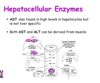

Enzymes Indicating Hepatocellular Damage

- these are the classic ones- leakage enzymes

- tell us there is damage to the hepatocytes

Hepatocellular damage - “leakage”

- these enzymes are readily available from the cytosol of the hepatocytes

- if there is damage to hepatocytes and it dies, the enzymes in hte cytoplasm will be released

- or some degree of damage to hepatocyte causes wall to release a little bit of cytoplasmic material

- blebosome: will have a bit of cytoplasmic material in it

- if you even just have a lot of blebbing from a large amount of hepatocytes, will still see an increase of these specific enzymes

Hepatocellular Enzymes: ALT and GLDH

- will increase about 12 hours after injury

- last for about 1-2 days

- more common in SA

large animals: ALT activity is very low!

Hepatocellular Enzymes: AST and ALT

- if you have marked muslce damage, you may see increase in AST

- need to differentiate if it is liver damage or liver damage

- CCK can help in this

- need to factor in how specific certain enzymes are to a tissue

Liver vs. Muscle

- CK can be a good indicator of muscle cell damge, but has a very short half life

- so the measurement of this parallel is not full proof